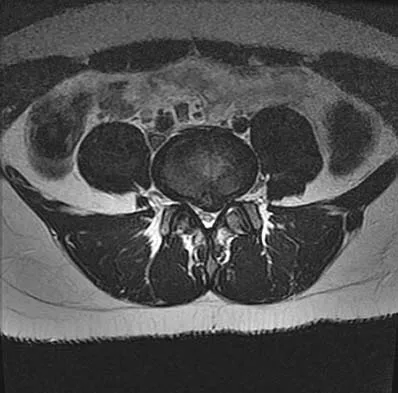

A 50-year-old man reports the onset of back pain and incapacitating pain radiating down his left leg posterolaterally and into the first dorsal web space of his foot 1 day after doing some yard work. He denies any history of trauma. Examination reveals ipsilateral extensor hallucis longus weakness. MRI scans are shown in Figures 19a through 19c. What nerve root is affected?

Detailed Explanation